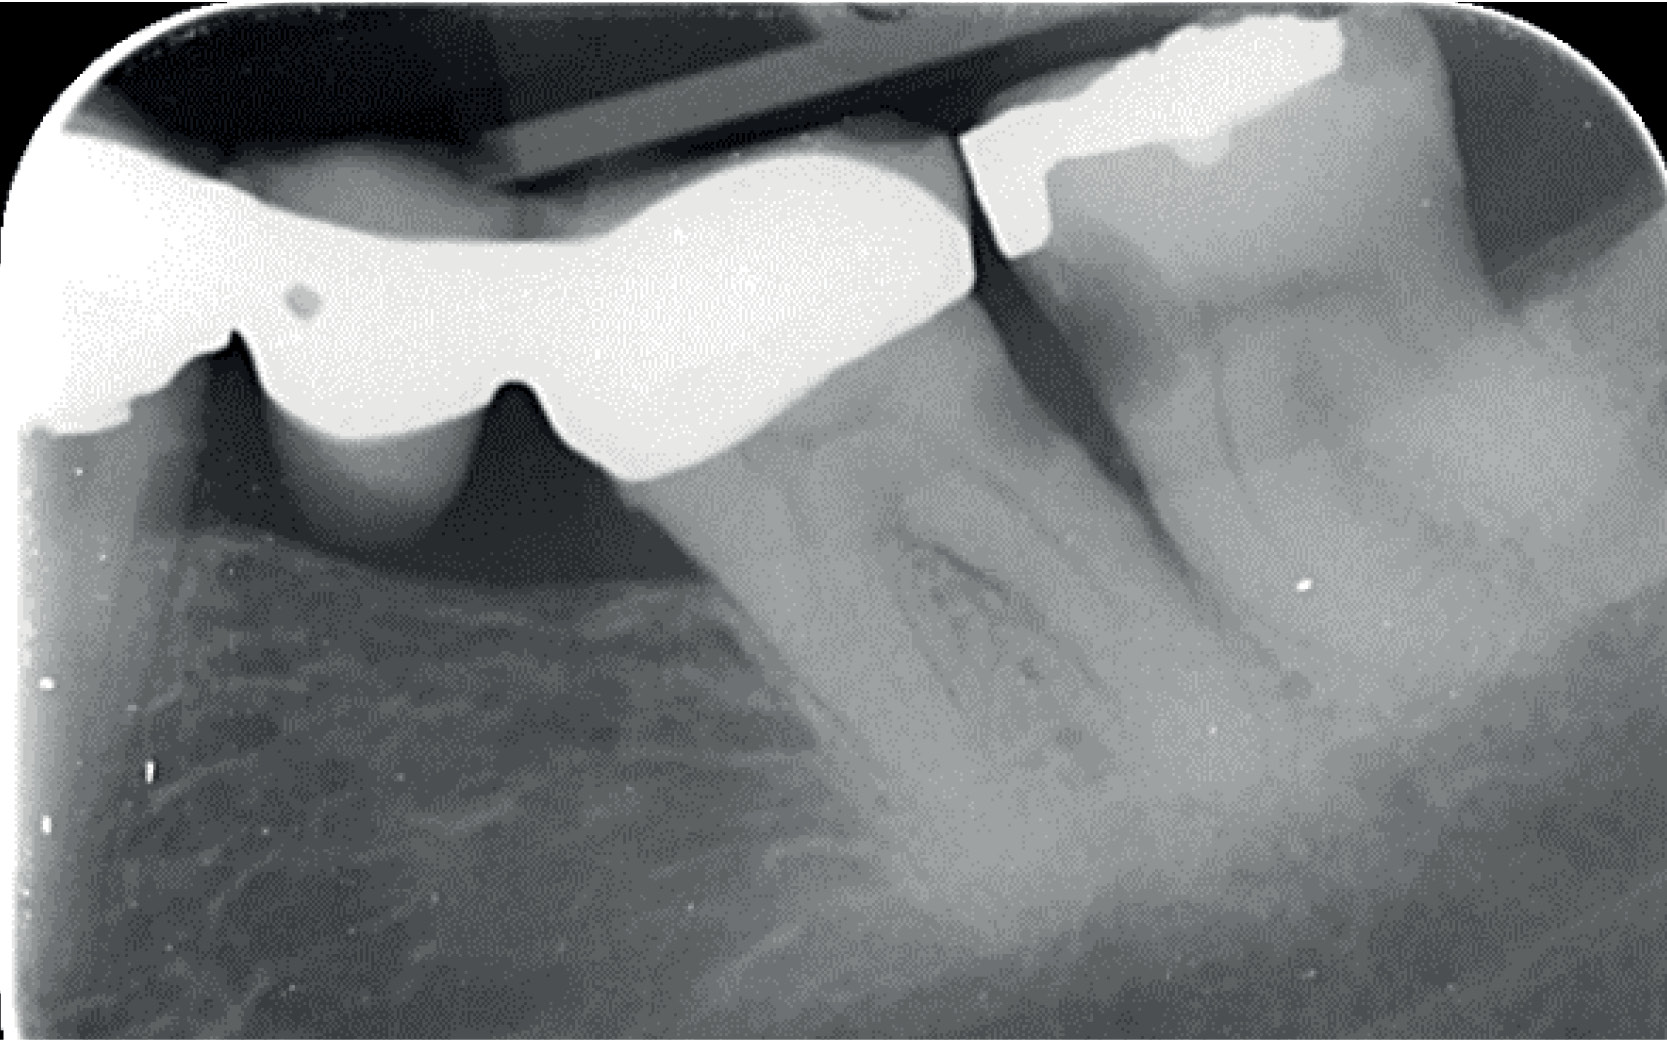

Fig. 2 Etter preparering

Distalt/okklusalt på 38 ses kroniske, inaktive karies, som står uberørt. Etter avsluttet ekskavering av 38 (figur 2), hvor allerede tidligere amalgam og karies er fjernet, påføres matrise. Det er benyttet et pre-konturert matrisebånd fra Top Dent i en klassisk Nyström matriseholder, samt en oransje trekile fra Kerr. Dette gir, i følge den nyere “golden standard ” (prekonturerte matrisebånd, gjerne også om plass med en separasjonsring), et optimalt kontaktpunkt og anbefales også av GC når man bruker Equia Forte for klasse II fyllinger.